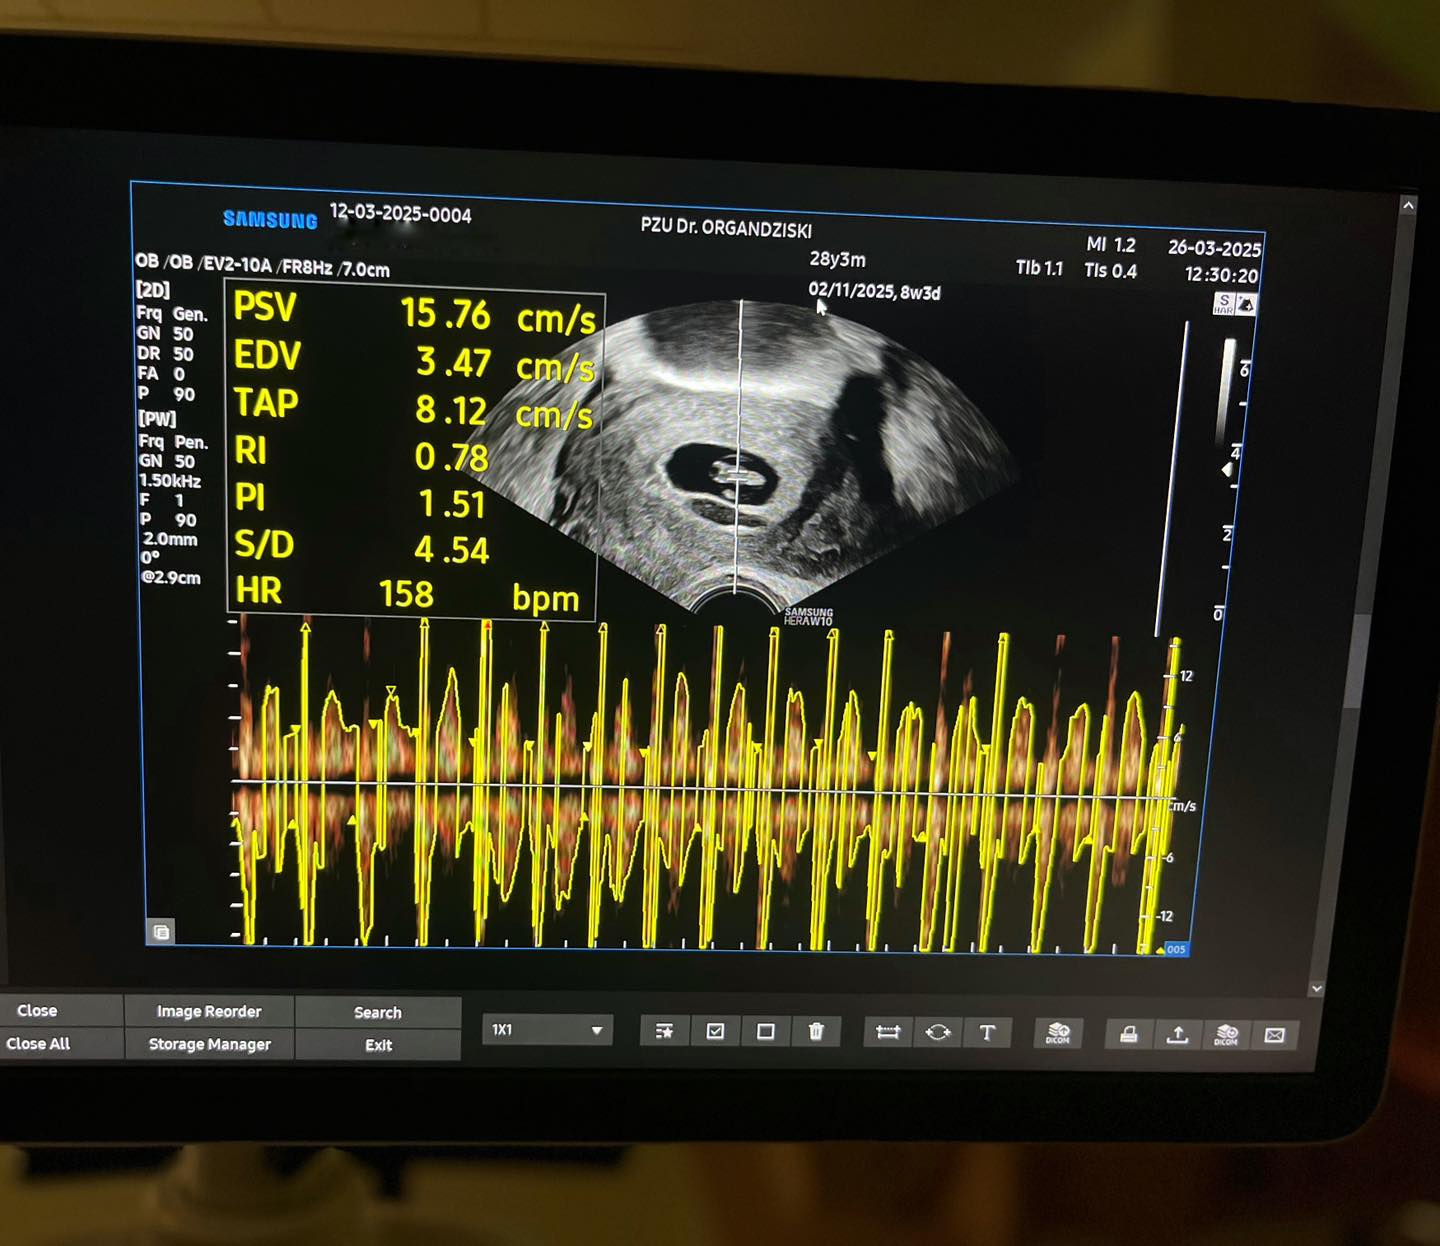

Резултат: Првата ин витро процедура во нашата болница заврши со создавање на 5 бластоцисти, а трансферот на два бластоцисти резултираше со позитивна бременост со два ембриони и потврдена срцева акција.